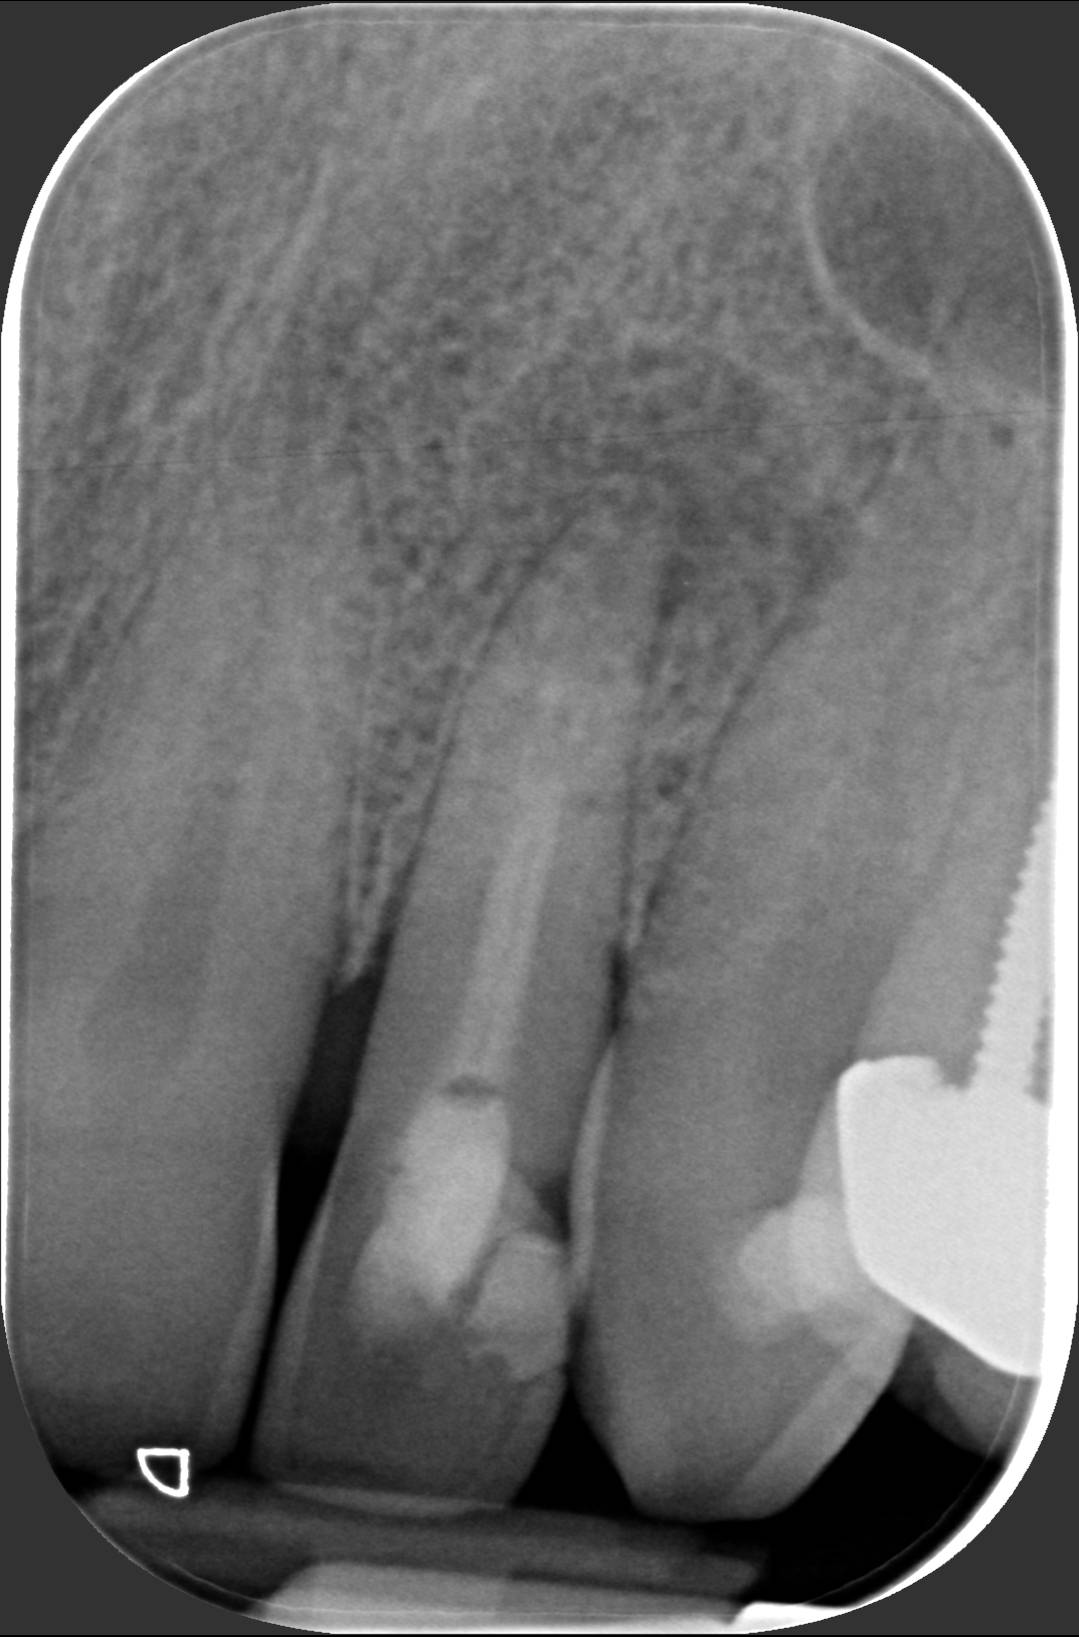

Il dentista ti dice che deve curarti tramite terapia canalare. Ti sei chiesto cosa succederà al tuo dente? All’interno del dente c’è un nervo. Se ne accorge chi ha una carie profonda: quando si infiamma fa un male insopportabile. Il classico mal di denti deriva proprio da qui. Non c’è farmaco che tenga, bisogna devitalizzare il dente malato, cioè togliergli il nervo. Ma non basta. Bisogna poi allargare lo spazio fino alla radice per pulire alla perfezione i residui del tessuto pulpare, dove era inserito il nervo. Si usano strumenti manuali e rotanti, montati su speciali “trapani”. Successivamente si eseguono numerosi lavaggi con siringhe di disinfettante. Alla fine bisogna chiudere tutto lo spazio creato con materiali speciali, che sigillano tutta la lunghezza del canale in modo tridimensionale. Dalla radiografia si vede se il lavoro è stato effettuato in modo corretto: l’otturazione canalare è quella striscia bianca che percorre tutta la lunghezza della radice, come vedi nella prima foto. Se invece si ferma a metà canale, come nella seconda foto, il lavoro non è eseguito a regola d’arte. Questo può portare al “granuloma”, un’infezione dell’apice del dente. In questo caso bisogna fare una nuova terapia canalare, eseguendo un “ritrattamento canalare”, togliendo la precedente otturazione canalare, ripulendo tutto, e otturando il canale fino in fondo, come si vede nella prima foto. Qui a Besana Brianza, il dott. Fabio Ballestrasse e il suo collaboratore dott. Vergani eseguono le terapie canalari come nella prima foto.